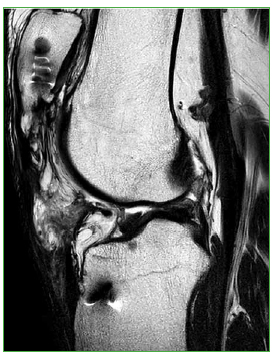

Figura 2.

Radiografías de rodilla, de perfil, comparativas. Se observa el ascenso de la rótula en la rodilla izquierda en comparación con la altura de la rótula en la rodilla derecha (índice de Insall-Salvati de 2 y 1,2, respectivamente).

Figura 3.

Resonancia magnética. Se visualiza una disrupción del tendón rotuliano con el consiguiente ascenso de la rótula. La distancia rótula-AT es de 9 centímetros.